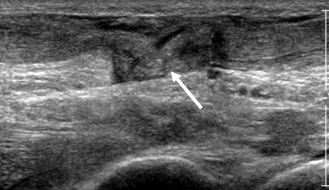

Echographie haute-fréquences

Comme pour l’échographie générale, l’échographie haute fréquence utilise les ultrasons.

Contrairement à l’échographie générale, aucune préparation n'est nécessaire.

C’est une technique non irradiante qui peut être utilisée chez la femme enceinte.